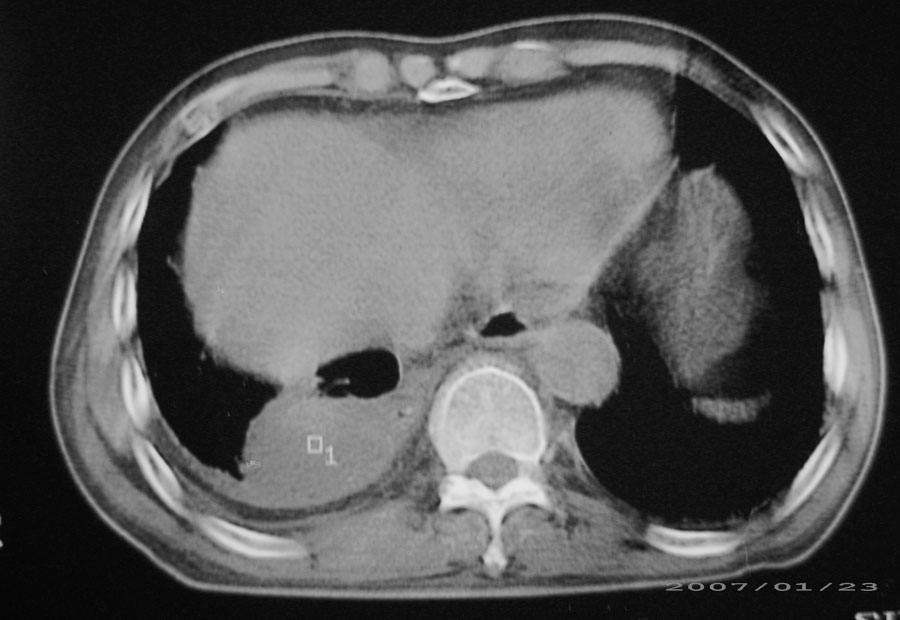

以下是引用hhcckk在2007-1-24 18:11:00的发言:[br]病灶周围胸膜反应比较明显,考虑炎症可能性大点,病人年龄较大,病灶成块状,肿瘤也不能排除,可可西里老师看片子的确很仔细,隔离肺暂时我觉得证据的说服力不大,上下层面显示条状影范围较长,可能是增厚的胸膜,可以做个增强鉴别一下

以下是引用天南地北在2007-1-24 18:00:00的发言:[br]1:右下肺内基底段类椭圆性肿快影:考虑1:右下球形肺炎2:右下肺隔离症,建议抗炎治疗后复查。[br]2:右肺及左下肺感染,右侧少量胸腔积液。